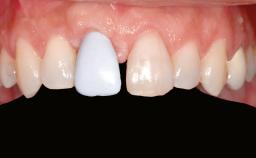

Ridge Preservation and Implant Placement for a Fixed Dental Prosthesis After a Car Accident

It is well known to clinicians that any removal of teeth will, over time, cause the dimensions of the alveolar ridge to be reduced by resorption of the bundle bone and by changes related to external modeling. This development is particularly evident in the crestal region with its thin buccal bone that consists of bundle bone almost entirely. The facial bone will rapidly resorb as blood supply from the periodontal ligament gets disrupted (Araújo and Lindhe 2005). There is no reason why traumatic tooth loss should not have the same consequences. It takes more than achieving implant osseointegration for a treatment outcome to be considered successful. No deficiency of bone or soft tissue is acceptable when an ideal esthetic outcome is the goal. Several articles (Sanz and coworkers 2011; Vignoletti and coworkers 2011) have reported on techniques of improving the alveolar ridge for implant treatment, notably focusing on protecting tissues from resorption.